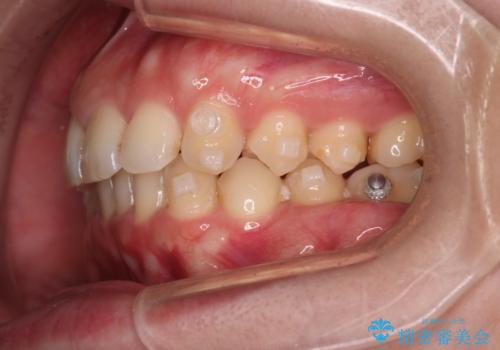

- 下の歯のがたつきを主訴に来院されました。

下の歯のがたつきと右の奥歯の噛みあわせ改善するために治療計画を立てることにしました。

右側臼歯部の咬合改善のために、臼歯部のみ部分的なワイヤー矯正を行い、咬合改善がみられてからインビザラインにて全体的な矯正を行なっていく治療計画を立てました。